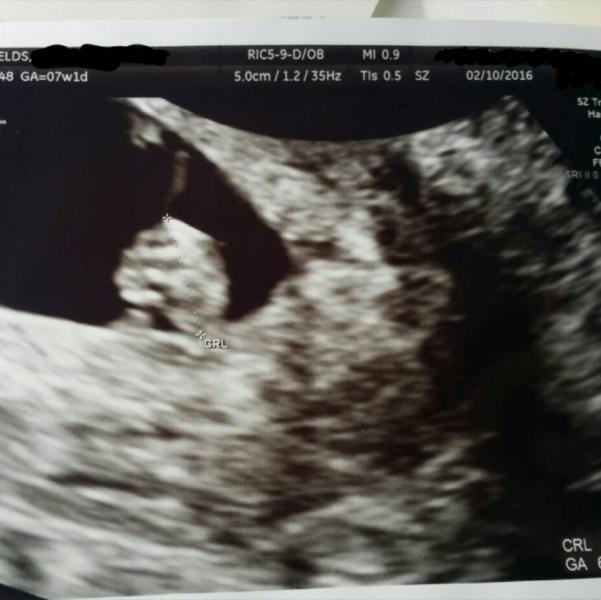

hello baby blob :) strong good heart beat :)

looks like a hand u see the 4 fingers lol but congratulations hun